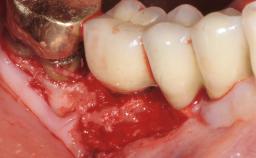

Peri-Implant Mucositis Treatment Outcomes on an Implant with a Submucosal Restoration Margin

Mauricio Araujo and Flauvia Matarazzo present this straightforward clinical case, demonstrating the potential effect of implant placement depth on the resolution of peri-implant treatment. A 42-year-old systemically healthy female patient, a non-smoker with no history of periodontitis, was treated at the Dental Clinic at the State University of Maringá, Brazil between 2008 and 2009, when she received five implants restored with single crowns at sites 14, 26, 27, 36, and 46. After delivery of the implant-supported prosthetic restorations, the patient was enrolled in the supportive peri-implant therapy (SPiT) maintenance program at the same university.